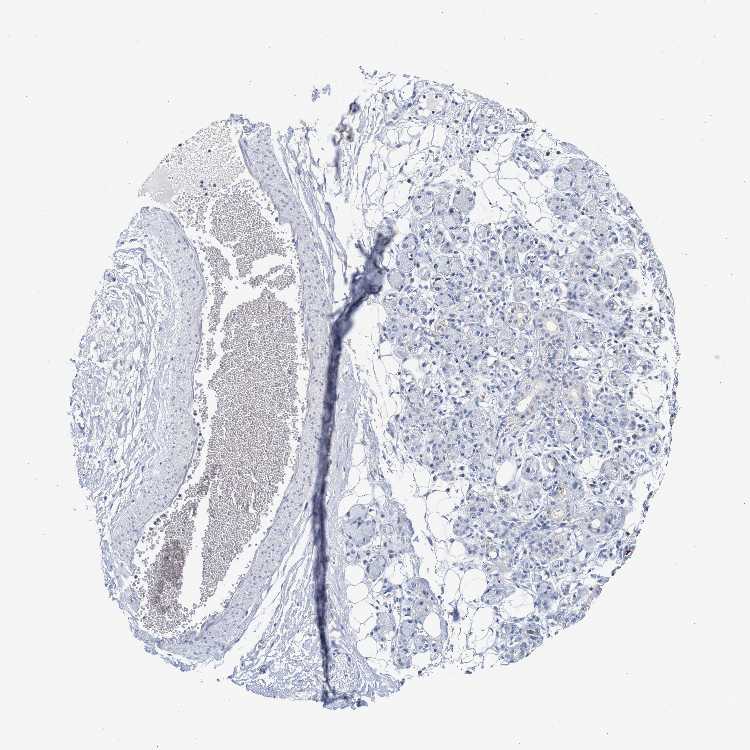

TISSUE PRIMARY DATA SOFT TISSUE Show tissue menu

SOFT TISSUE 1 - Antibody stainingi

Antibody staining in the annotated cell types in the current human tissue is reported as not detected, low, medium, or high, based on conventional immunohistochemistry profiling in selected tissues. This score is based on the combination of the staining intensity and fraction of stained cells.

Each image is clickable and will lead to virtual microscopy that enables deeper exploration of all samples and also displays staining intensity scores, fraction scores and subcellular localization as well as patient and tissue information for each sample.

Antibody HPA021165Antibody HPA021753Antibody HPA021760

Chondrocytes Not detected-Not detected

Fibroblasts Not detectedNot detectedNot detected

Peripheral nerve Not detectedNot detectedNot detected